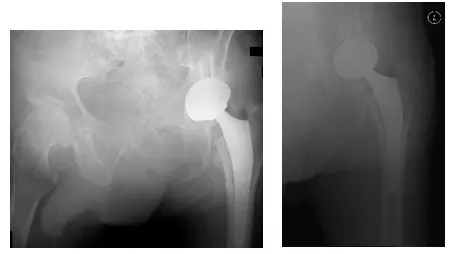

X-Rays show severe degenerative changes of the left hip joint including loss of joint space and deformity of left hip

X-Rays show post-operative changes of left TKA with a new femoral head prosthesis